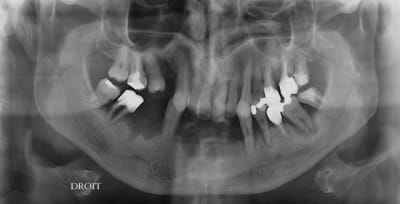

Autre cas qui peut poser un problème similaire .

Nouvelle patiente vu en urg pour resceller son bridge 22 24.

22 et 24 total recariées, tres mobiles.

je rescelle et on decide de se revoir pour faire le point.

55 ans, pour elle , pas question de rester sans dent, ni de dentier, même pendant 3 mois.

Mais sait pertinemment qu'elle est dans une situation... délicate !

Que peut on lui proposer ? doit on lui dire que l'on a pas de baguette magique ?